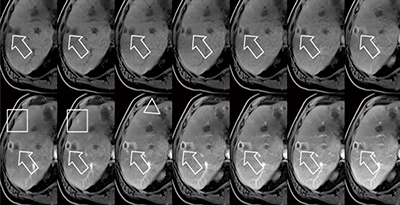

まず,TWIST-VIBEについてであるが,その目的は高い時間分解能の3Dダイナミック撮像にある。造影4D-MRAを撮像するためのTWIST法と,3Dダイナミック撮像法であるVIBE法を組み合わせた,新しい3Dダイナミック撮像法である。TWIST法は,低周波成分と高周波成分を別々に,交互に信号収集することによって時間分解能を上げるためのエコーシェアリング型の造影4D-MRA撮像である。VIBE法の撮像においてエコーシェアリング型の信号収集をすることによって,さらに高い時間分解能の3Dダイナミック撮像が可能になる。通常3Dダイナミック検査の場合,長時間の息止め検査が必要で,被検者に対する負担が大きかった。また,その撮像画像の質は,被検者の状態や検査環境への依存度が高かった。TWIST-VIBEによって,さらに短い息止め時間での高画質撮像を可能とし,短時間での動脈相のダイナミック撮像などが安定して行えるようになる(図1)。

図1 TWIST-VIBEによる動脈相のダイナミック撮像例